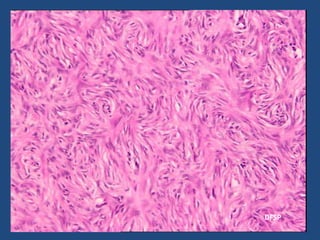

Fibromatosis

1 Proliferation of well-differentiated fibroblasts

2 Infiltrative pattern of growth

3 Presence of a variable (but usually abundant)

amount of collagen between the proliferating

cells

4 Lack of cytologic features of malignancy

5 Scanty or absent mitotic activity

6 Aggressive clinical behavior characterized by

repeated local recurrences but lack of capacity to

metastasize distantly

• Grossly, these lesions are often large, firm,

and whitish, with ill-defined outlines and an

irregularly whorled cut surface. They often

arise in a muscular fascia.

• Microscopically, most of the proliferating cells

have features intermediate between those of

fibroblasts and smooth muscle cells

The spindle cells of fibromatosis grow diffusely

between skeletal muscle fibers